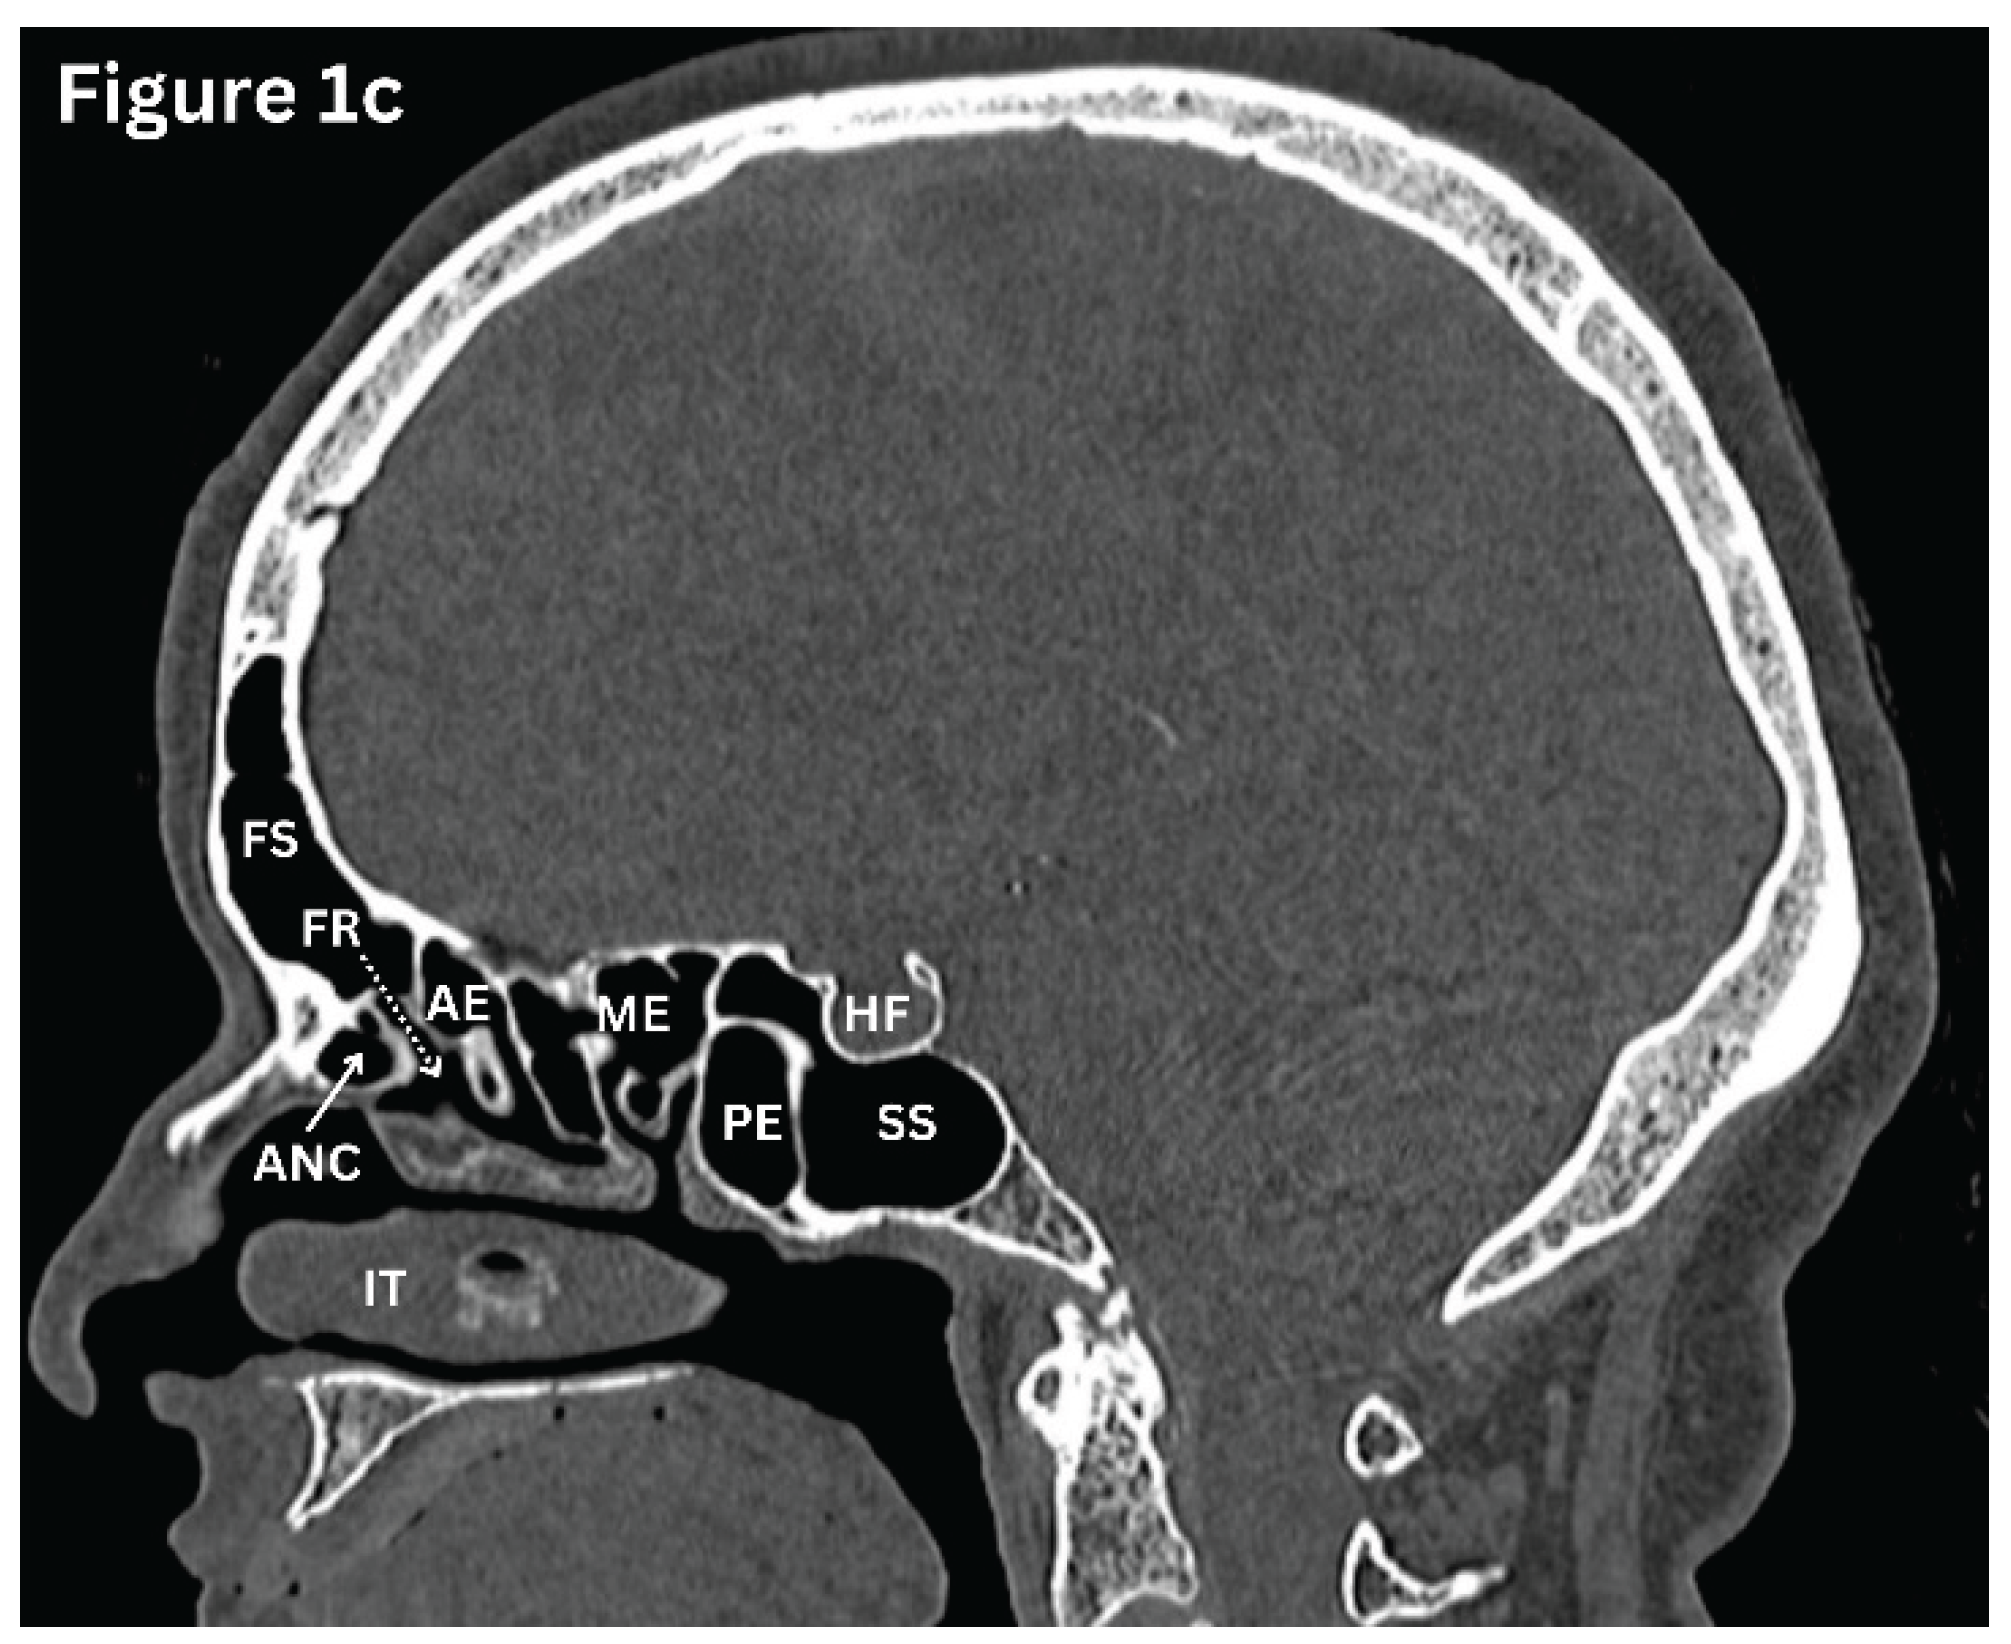

Figure 1. a-c: HRCT paranasal sinuses (bone window). a-Coronal; b-Axial; c-Sagittal images. NS: Nasal septum; MT: Middle turbinate; IT: Inferior turbinate; MM: Middle meatus. I: Infundibulum; UP: Uncinate process; MA: Maxillary antrum; MS: Maxillary sinus; AE: Anterior ethmoid sinus; ME: Middle ethmoid sinus; PE: Posterior ethmoid sinus; SS: Sphenoid sinus; FS: Frontal sinus; EB: Ethmoid bulla; CB: Concha bullosa; LP: Lamina papyracea; FR: Frontal recess; ANC: Agger nasi air cell; HF: Hypophyseal fossa.

The frontal sinuses are unique among the paranasal sinuses in that they are absent from birth and develop later in childhood. They are the most superiorly positioned sinuses and are located within the frontal bone. The frontal sinuses exhibit marked variation in size and symmetry among individuals. Drainage of the sinus occurs via the frontonasal duct into the middle meatus.

(Figure 1c) Sensory innervation is provided by the supraorbital nerve, while vascular supply is derived from branches of the ophthalmic artery. Due of their highly variable anatomy and close proximity to the anterior cranial fossa and the orbit, the frontal sinuses present challenges during surgical intervention and carry an increased risk of intracranial complications in the context of frontal sinusitis [1,2].

Sphenoid Sinus

Sphenoid sinuses are a pair of sinuses separated by a septum and situated deep within the sphenoid bone. (Figure 1c) The sphenoid sinus demonstrates considerable variation in size. When underdeveloped, it lies anterior to the pituitary fossa, but with increasing pneumatisation, it extends beneath the fossa. Posterior extension into the basiocciput may occur, and in extensively pneumatised sinuses, aeration can also involve the greater wing of the sphenoid and the pterygoid processes. The sphenoid sinus drains into the sphenoethmoidal recess. It is closely related to the optic nerve, cavernous sinus, pituitary gland, and internal carotid arteries. Even minor pathology in this region may result in significant neurological or visual symptoms [1,2].